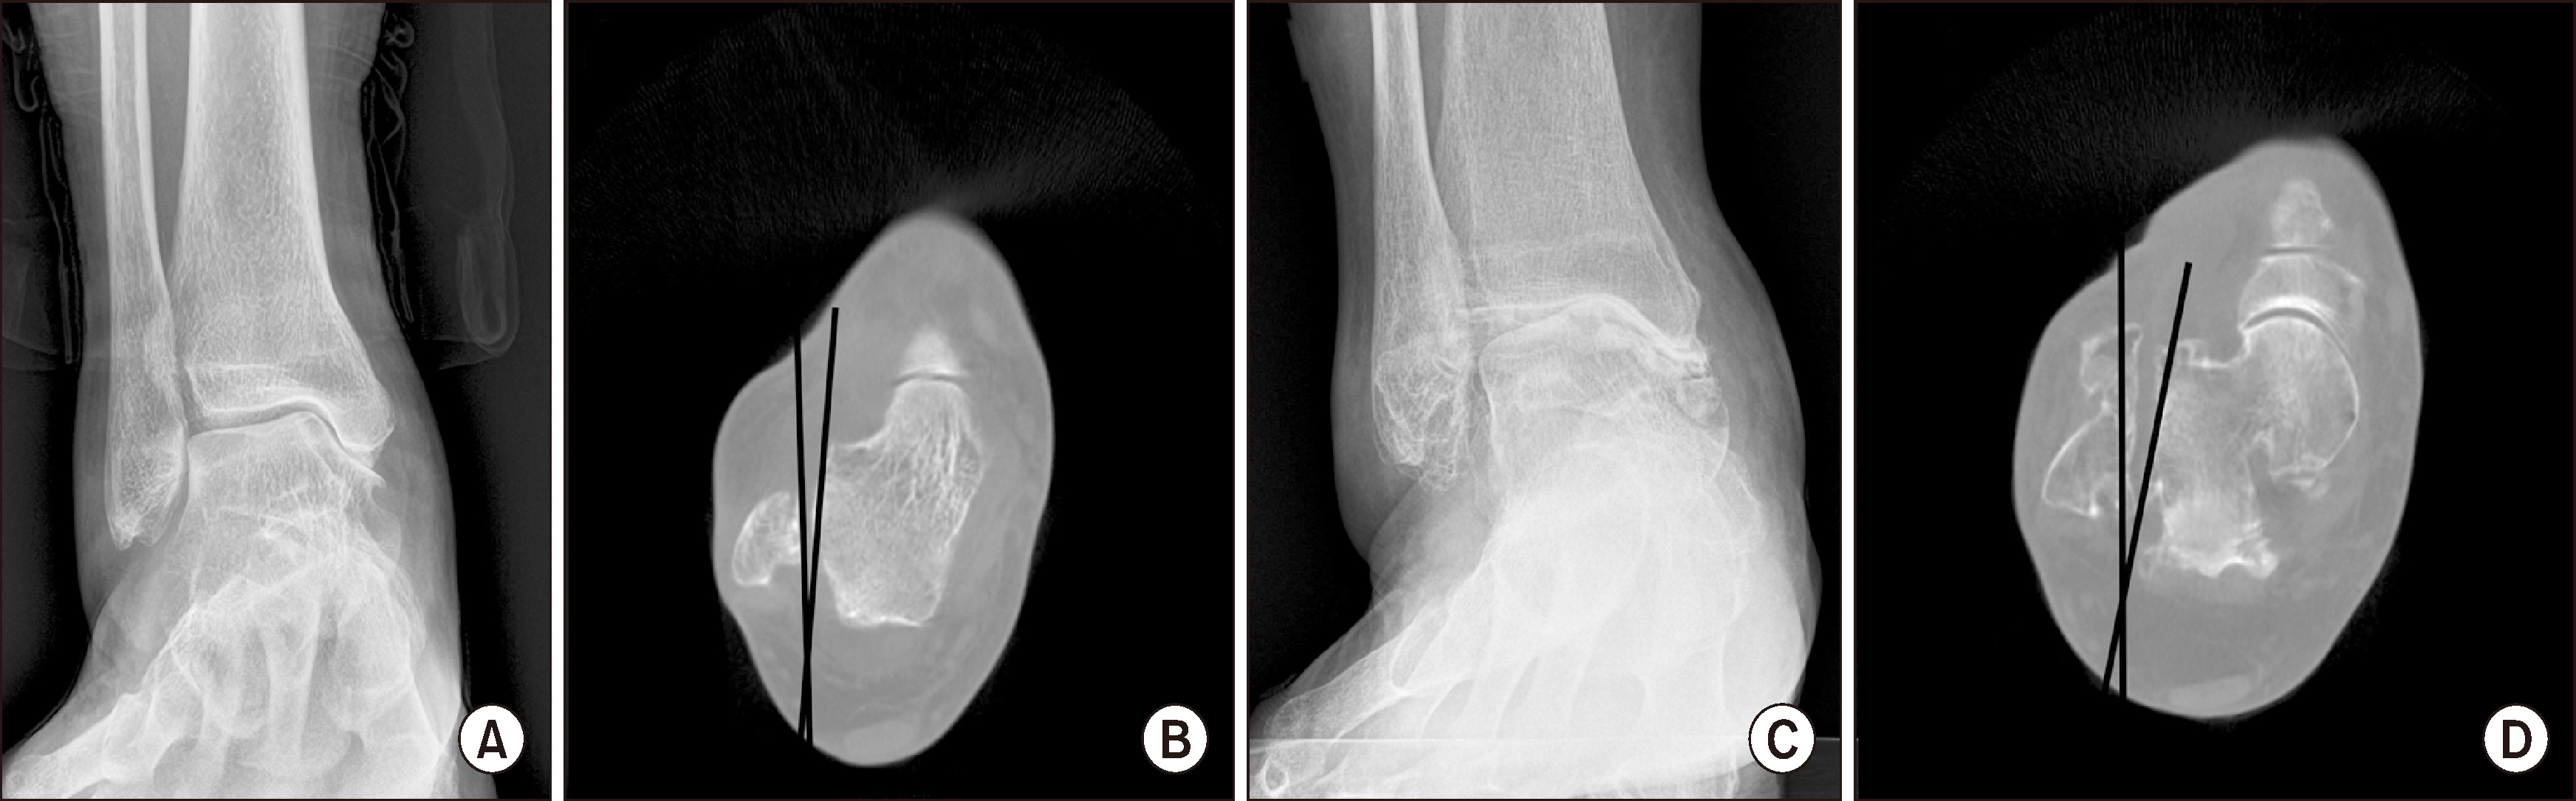

발목 관절염의 진단에서 WBCT의 활용은 발목관절의 격자(mortise)에서 거골의 위치를 파악하는 것에서 시작되며 거골 위치의 병적인 상태는 관절염의 중증도를 시사할 수 있다. Kim 등14)은 거골 회전 비율(talus rotation ratio)을 이용하여 축상면(axial plane)에서 비정상적인 거골의 내회전을 정량화하였으며, 내반 관절염 환자에서 이러한 거골의 내회전이 유의하게 증가함을 확인하였다(Fig. 5). 또한, 중등도보다 심한 내반 관절염 환자에서 비정상적인 거골의 내회전이 더 빈번하게 관찰됨을 보고하였다. 이러한 연구 결과는 발목 관절염 환자를 진단할 때, 기본적인 단순 방사선 검사에서 쉽게 평가할 수 있는 관상면(coronal plane) 및 시상면(sagittal plane)의 변형뿐만 아니라, WBCT를 이용하여 축상면의 변형까지 고려해야 함을 시사한다.

Figure 5

Abnormal internal rotation of the talus in the axial plane in varus ankle arthritis. (A) Plain weight-bearing anteroposterior ankle radiograph of a patient with moderate varus ankle arthritis, (B) WBCT axial image showing the talus abnormally internally rotated against the lateral malleolus, (C) plain weight-bearing anteroposterior radiography of patient with severe varus ankle arthritis, (D) WBCT axial image demonstrating more frequent and pronounced abnormal internal rotation of the talus in the axial plane. WBCT: weight-bearing computed tomography.